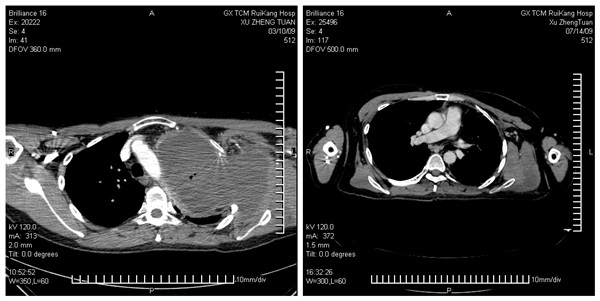

至今历时2年半时间,经过3次CT和磁共振检查,均提示该肿瘤逐渐缩小,最后一次复查(2011年8月15日CT)见肿瘤已经缩小至5cm×3cm,仍为坏死组织,左肺已经完全复张,左上肢功能已经完全恢复,没有发现新病灶。

治疗前、后CT片(前图右侧为肿瘤)